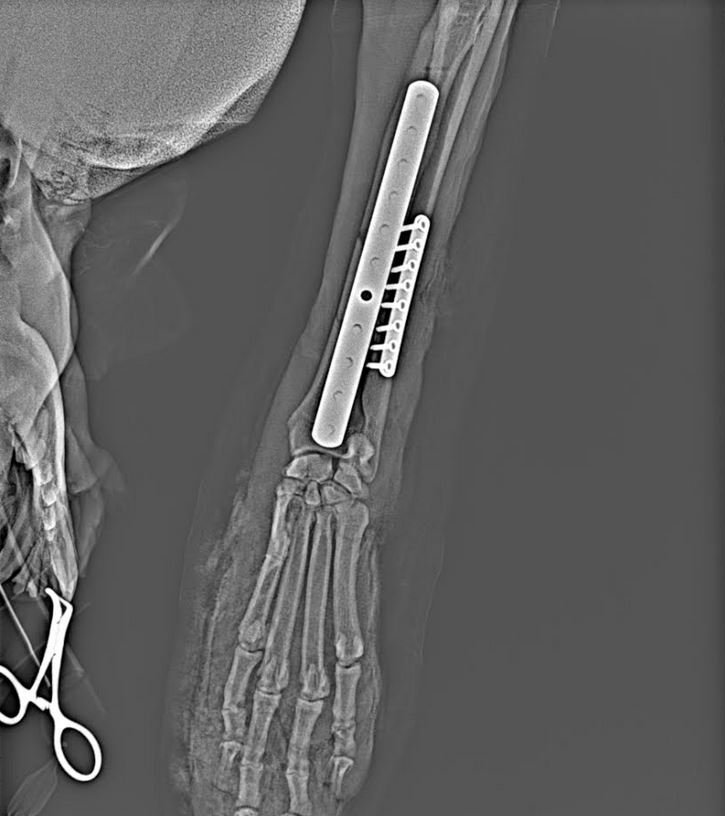

Veronika: ,, S panem Padevětem jsem se seznámila včera za hodně smutných okolností. Cestou pro malou do školky jsem ho našla klečet zoufalého u silnice nad jeho psem Blackem. Stala se úplně pitomá schoda okolností. Pán šel venčit Blacka k rybníčku a cestou mu házel míček. Blackovi se ale jednou nepodařilo míč chytit a odrazil si ho čumákem přímo do silnice, kde za normálních okolností jezdí tak desetina aut, ale jelikož tudy teď vede objížďka.....zkrátka Black naběhl přímo pod kolo autobusu, který mu doslova sešrotoval přední nohu. Jeden další kolemjedoucí pán nám pomohl pejska odnést ke mě do auta (díky neznámý pane:-)...)a odvezla jsem Blacka i s páníčkem na Veterinární kliniku. Než jsme tam dojeli pes upadl do šoku, což je akutní život ohrožující stav a bylo potřeba ho stabilizovat. Bude žít, ale musí podstoupit poměrně náročnou operaci nohy. Kostní operace u psů jsou finančně hodně nákladná záležitost a to je vlastně důvod proč to tu celé píšu. Napadlo mě že každý v domácnosti čas od času používáme med. Kupte si med od pana Padevěta, pomůžete mu tím zaplatit náročnou operaci pro jeho psa. Díky..."